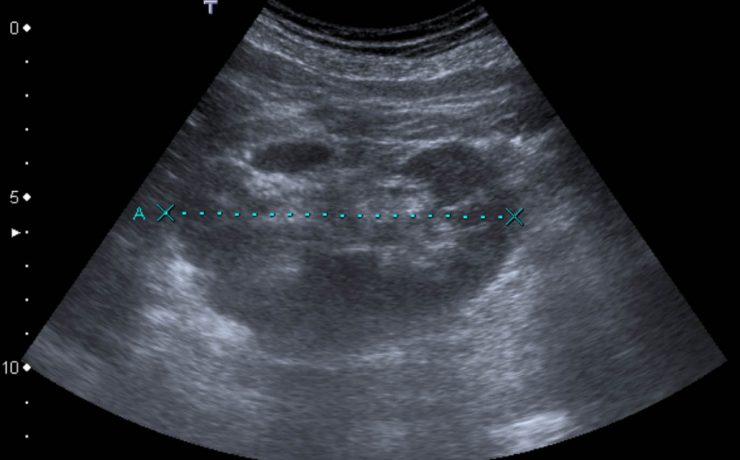

El ultrasonido en algunas afectaciones de la tiroides

La glándula tiroides está ubicada en la región anteroinferior del cuello, en el compartimento infrahioideo. Se halla por delante de los primeros anillos traqueales y de la zona lateral de la laringe. El volumen de la glándula puede ser un poco mayor en la mujer, a pesar que presenta múltiples